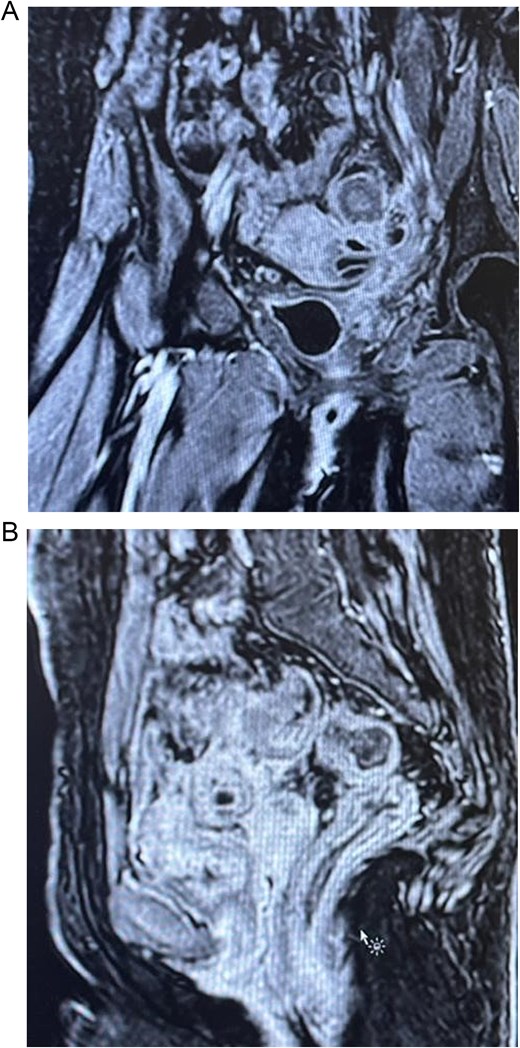

Computed tomography (CT) abdomen and pelvis showed perforated sigmoid diverticulitis, extraluminal collection measuring 3 × 1.8 cm, fistula formation extending to left aspect of urinary bladder dome, and another fistula possibly extending to anterior wall of rectum (Fig. 1).

(A) Axial section of the abdominopelvic CT scan showing the colovesical fistula. (B) Axial section of the abdominopelvic CT scan showing the diverticular disease of the colon.